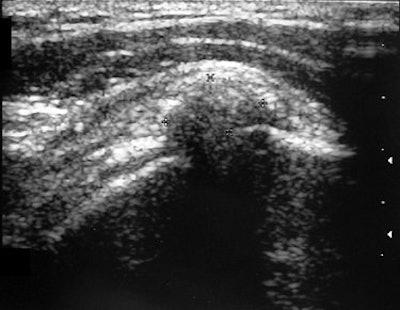

| A 39-year-old woman with calcific tendinitis for six months. Before treatment, longitudinal sonogram of supraspinatus tendon shows focus of calcification and acoustic shadow. |

According to the results, the suprasinatus tendon was involved in 57 of the 67 shoulders. In 83.6% of the cases, radiographs showed dense, homogenous, and well-defined calcifications. All calcifications were visible on sonography with 58.2% demonstrating a strong acoustic shadow. In terms of calcium extractions, the mean volume per patient was 0.4 mL with no calcium extracted in 25% of the subjects.